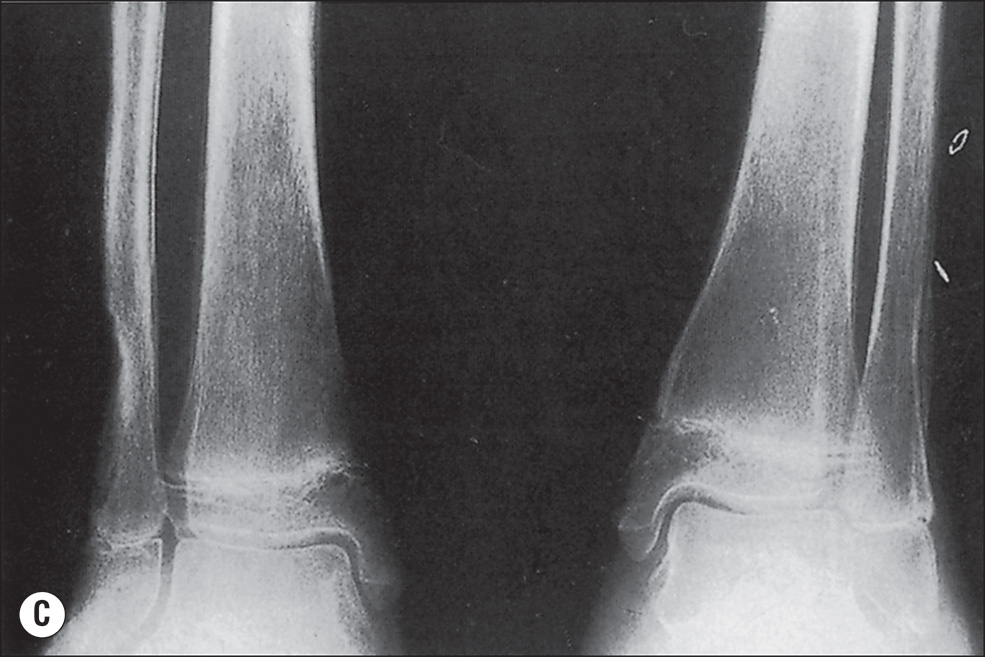

The more extensive the burn and the greater the number of complications, the longer the patient may be confined to bed and relatively immobile. The onset of osteoporosis is accelerated, and its intensity is more marked in the burn illness that features a hypermetabolic state. Klein et al. found that osteoblasts and probably osteocytes underwent apoptosis in response to the glucocorticoid stress hormones. The overall effect of burn is catabolic, and muscle wasting is also noted. If a single extremity of an otherwise normal person is immobilized for a long time because of local trauma, as with a fracture, loss of bone density can be easily seen on plain radiographs. So, with burns isolated to the extremities, the bones of affected extremities become osteoporotic, and in persons with generalized burns, the bones of deeply burned extremities may show more profound mineral loss than is observed in nonburned extremities or in the axial skeleton ( Fig. 41.1 ). This tendency for more osteoporosis in severe burns was also noted by Pandit et al., who found that 56% of postburn patients had radiographic evidence of osteopenia. Van der Wiel et al. found in an x-ray absorptiometry study of 16 adults with fractures of one tibia that there was eventual loss of bone mineral density in the contralateral femur and in the lumbar spine but to a lesser degree than in the ipsilateral femur. These findings, although not strictly analogous to those observed in burns, nevertheless point to the occurrence of generalized osteoporosis in other trauma states and the difference in loss of bone density relative to local factors. In fractures or in burns, impaired mobility and local hyperemia could account for this difference.

(A) Advanced osteoporosis in the hands of a 14-year-old boy 9 months after a 100% total body surface area burn. All growth plates are open. (B) At 24 months after injury, osteoporosis persists, and there is irregular closure of the metacarpal and phalangeal growth plates. (C) At 8 months after injury, the growth plates of the distal tibiae and fibulae remain open. (D) At 24 months after injury, the distal growth plates of the tibiae and fibulae are closed. Other major growth plates remain open. Osteoporosis is unchanged.